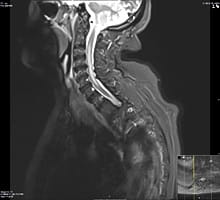

Neuromyelitis Optica

Neuromyelitis Optica (NMO) or Devic’s disease is a severe autoimmune inflammatory condition that preferably involves the optic nerves and the spinal cord causing extensive inflammation and tissue damage. It is caused by specific antibodies against water channels in the central nervous system and often leads to significant disability if not treated aggressively and in a timely manner. NMO is more common in African American and Asian populations and is not uncommonly misdiagnosed as MS which can lead to improper and potentially harmful treatment. Learn more about Neuromyelitis Optica.

An MRI image showing a long area of inflammation in the spinal cord in a patient with NMO.